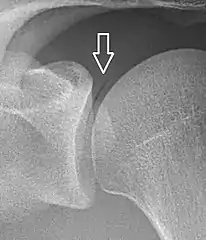

Pneumarthrosis is the presence of air in a joint. Its presentation on radiography is a radiolucent cleft often called a vacuum phenomenon, or vacuum sign.[7] Pneumarthrosis is associated with osteoarthritis and spondylosis.[8]

Pneumarthrosis is a common normal finding in shoulders[7] as well as in sternoclavicular joints.[9] It is believed to be a cause of the sounds of joint cracking.[8] It is also a common normal post-operative finding at least after spinal surgery.[10] Pneumarthrosis is extremely rare in conjunction with fluid or pus in a joint, and its presence can therefore practically exclude infection.[8]